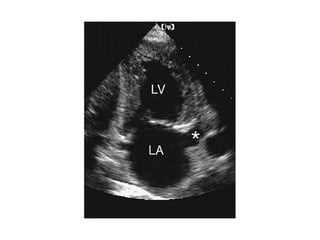

FALSE TENDON IN LV APEX

From the apical five-chamber view, simultaneous recording of

aortic outflow and mitral inflow can be performed.

This permits isovolumic relaxation time (IVRT) to be measured.